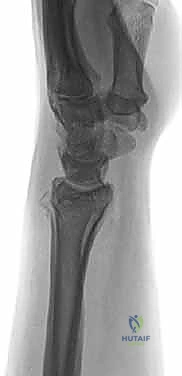

بروتوكول التصوير الطبي المتقدم

لا يكتفي الدكتور هطيف بالفحص السريري، بل يعتمد على أحدث تقنيات التصوير لضمان "الأمانة الطبية" في التشخيص:

1. الأشعة السينية (X-rays): بوضعيات متعددة (أمامية خلفية، وجانبية دقيقة). الوضعية الجانبية الحقيقية (True Lateral) حاسمة لاكتشاف أي خلع جزئي في المفصل (DRUJ).

2. الأشعة المقطعية ثلاثية الأبعاد (3D CT Scan): تُستخدم في الكسور المفتتة أو كسور رأس الزند المفصلية المعقدة، حيث تعطي خريطة دقيقة للجراح قبل الدخول لغرفة العمليات.